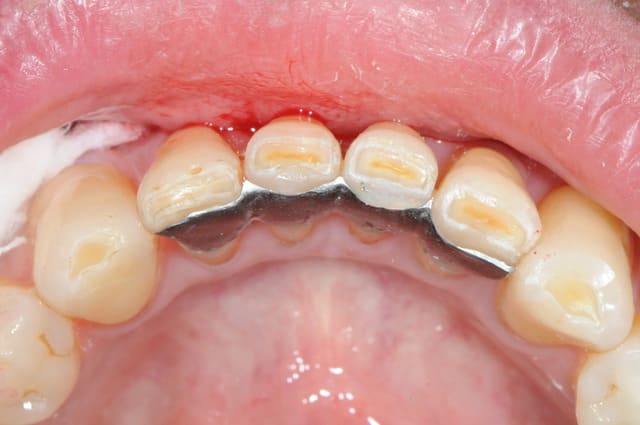

la suite pour blette que ça interesse .je suis agréablement surpris de la de la rétention et de la stabilité données par cs 2 pins dentinaires

photos lundi ou mardi scellé

Brideg coll  001 mbookn - Eugenol

Brideg coll  002 cztmdu - Eugenol

Brideg coll  003 jqzbus - Eugenol

Brideg coll  004 kfuszo - Eugenol